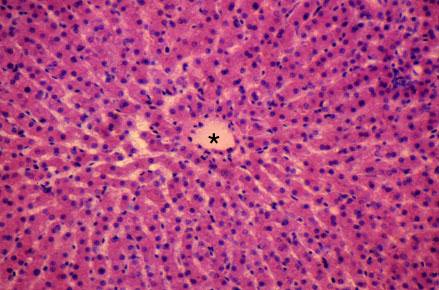

VIII-29, Slide 64, Liver (H&E). Hepatocytes are arranged in cords or plates. Sinusoids are capillaries separating plates of hepatocytes. The blood in sinusoids drains into a central vein (*).